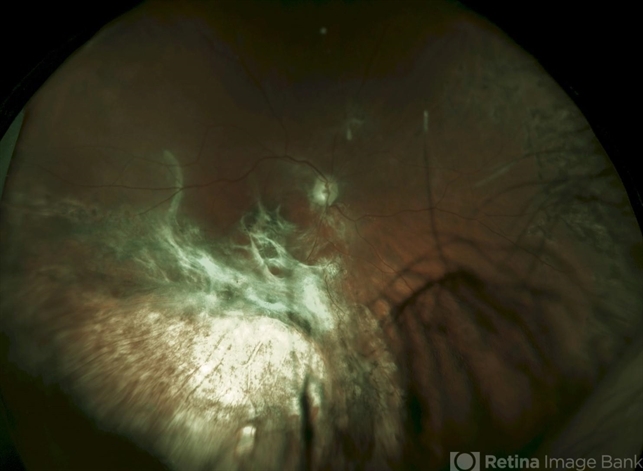

- choroidal rupture

- Sandra Boglione, Ross Eye Institute, University at Buffalo, Jacobs School of Medicine, Buffalo, NY

Fundus camera

Optos - Description

- Severe choroidal blow out caused by a suprachoroidal hemorrhage. There was a dense VH, and ultrasound showed a possible tear in the mid-periphery. Intraoperatively, a severe choroidal rupture secondary to a suprchoroidal hemorrhage was found temporally and a separate rhegmatogenous retinal detachment was found nasally. This photo was taken after silicone oil had been removed. The initial cause of injury was from a hockey ball in a young man.